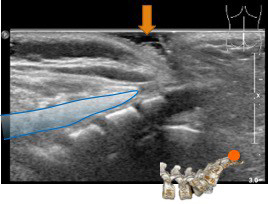

l’échographie médullaire

est un excellent examen à la naissance, mais sa performance diminue rapidement du fait de l’ossification du rachis.

l’échographie permet d’identifier correctement une fossette banale, qui rejoint le coccyx donc à distance de l’extrémité du canal dural.

elle permet également de montrer le niveau de la terminaison médullaire qui doit être au minimum en L2.

si l’échographie de bonne qualité est normale, elle dispense de l’IRM.